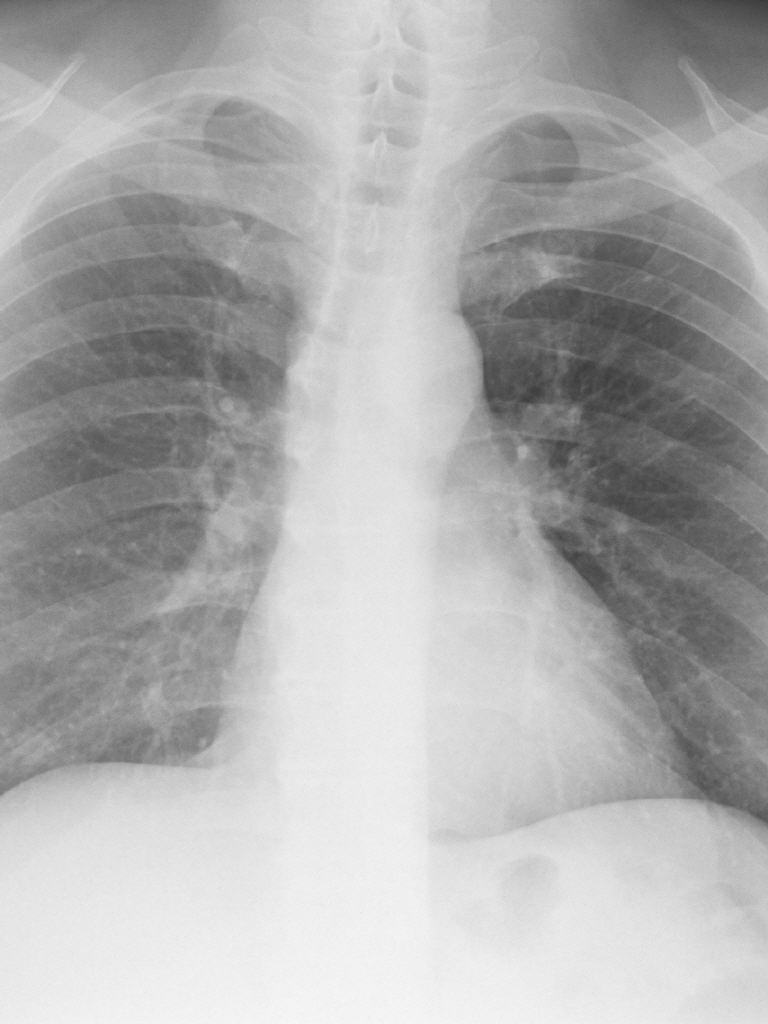

- Lungenaufnahmen